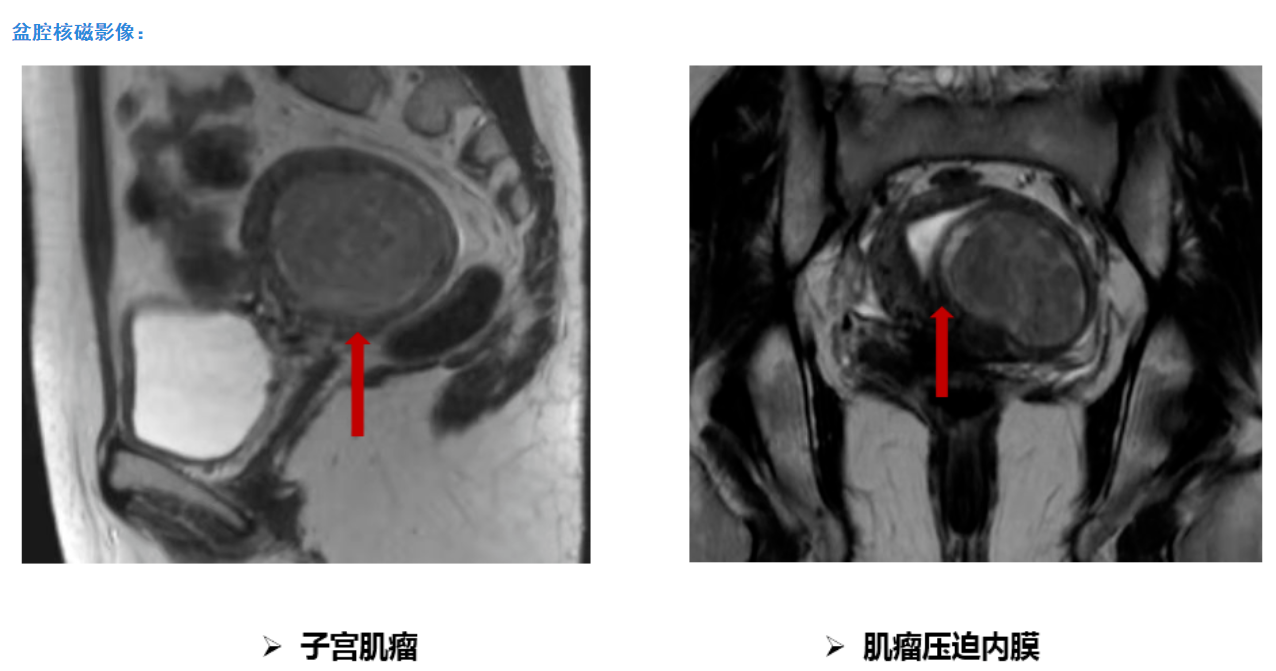

平素月经规律,5-6天/29天,量中,痛经(-),LMP:2021-10-24。3年前体检查妇科彩超提示子宫肌瘤,直径约2cm。无相关不适症状,建议定期复查。期间不定期复查彩超提示子宫肌瘤逐渐增大。10个月前无明显诱因出现经量增多,约为原来的2-3倍,伴血块,经期延长,最长达14天,月经周期未见明显改变,口服药物(具体不详)治疗未见好转。为明确诊治就诊我院门诊,查妇科彩超提示:子宫后壁可见6.99x5.35cm的低回声团,向前压迫子宫内膜,宫腔可见深度约0.55cm的无回声区,宫颈形态规则,内未见异常回声,子宫左侧可见1.75x1.21cm的低回声团,与子宫关系密切。建议住院手术治疗。